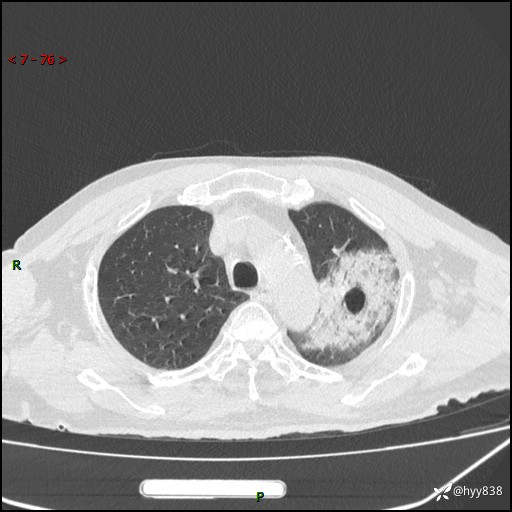

胸部CT平扫(2024.7.24)